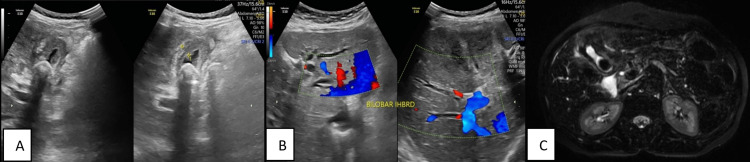

Figure 14. GB carcinoma. (A) Transabdominal USG shows irregularly thickened GB wall with cholelithiasis; (B) Transabdominal USG shows bilobar intrahepatic biliary dilatation; (C) Axial three-dimensional reconstructed image shows irregularly thickened GB wall with surrounding T2 hyperintensity and cholelithiasis.

GB: gallbladder

In the majority of patients, a correct diagnosis of the cause of obstruction was made through MRCP. The most common malignant cause of biliary obstruction detected on MRCP was gallbladder carcinoma (Figure 14), followed by cholangiocarcinoma. Excellent diagnostic performance was noted in detecting all malignant lesions.